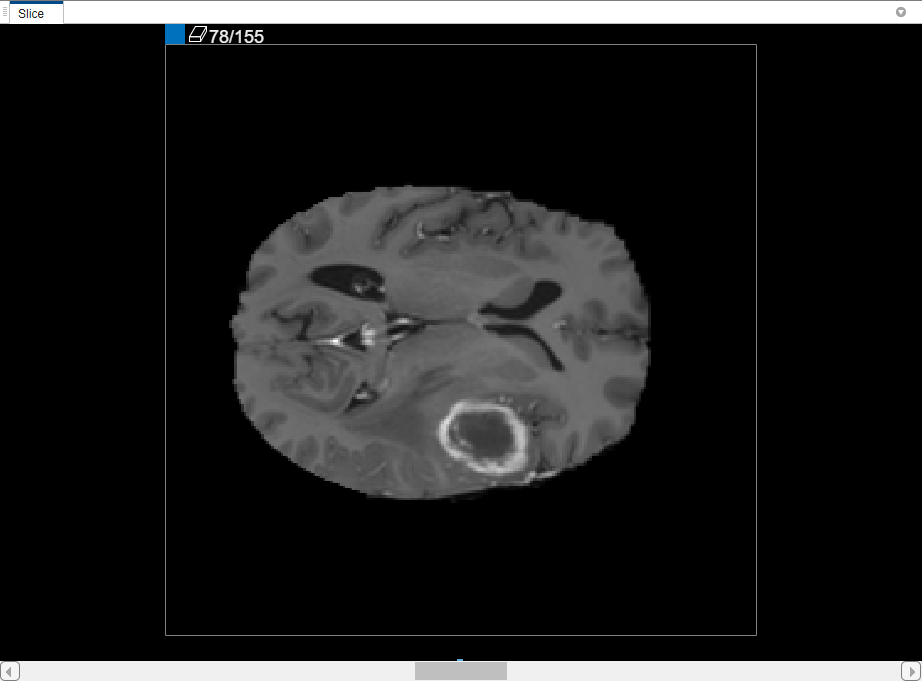

In the 3-D Display pane, you can rotate the volume to examine the data from every angle, using the mouse. You can also customize the display of the volume in the 3-D Display tab in the app toolstrip. For example, if you have metadata that describes the relative size of the voxels, you can specify it in the Spatial Referencing part of the 3-D Display tab in the app toolstrip. To improve your view of the data, you can change the background color used in the 3-D display, modify the threshold and opacity of the display, and include orientation axes with the display, as shown in the figure below. With the brain MRI data, you can see the tumor in the temporal lobe that you want to segment.

You can also view each slice of the volume in the Slice pane. Use the slider at the bottom of the pane to move from slice to slice. You can see the tumor on slice 35 through slice 88. By default, the Slice pane displays the volume oriented along the X-Y axis, but you can change this using buttons in the Orientation section of the toolstrip on the Segmenter tab. The Slice pane is also where you use drawing tools to define the mask.